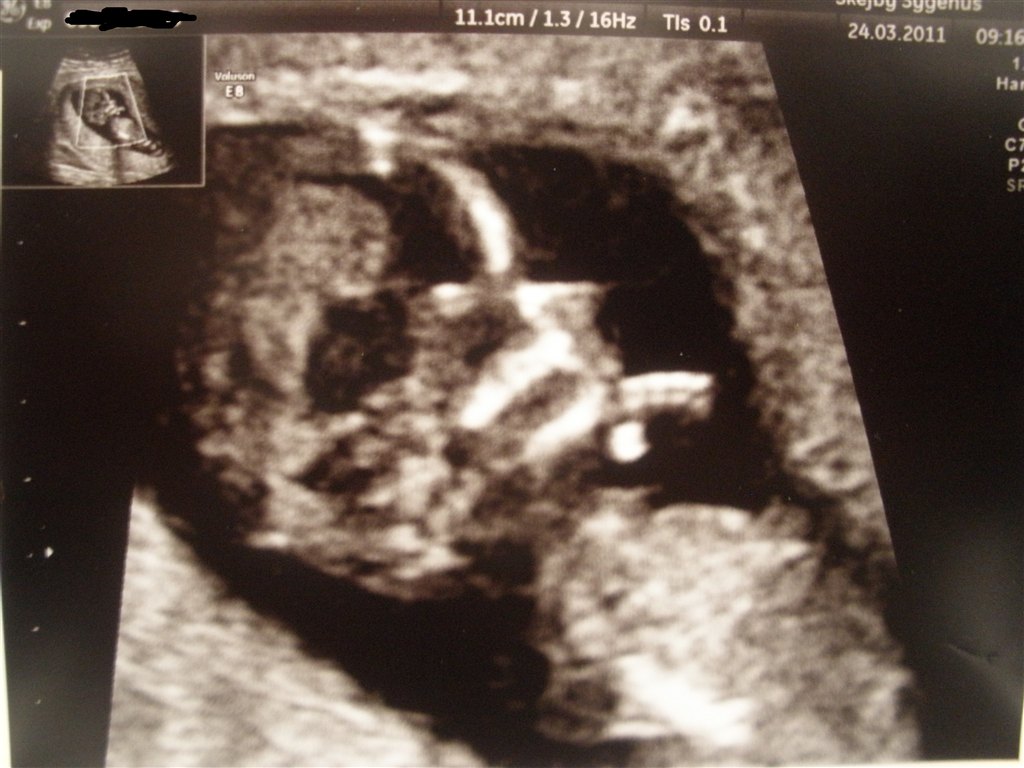

De to sidste er fra NF, hvor jeg var 12+